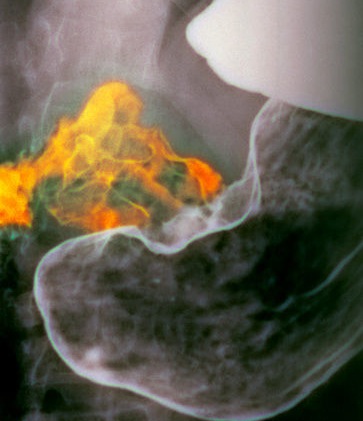

Рентгенография рака дистальных отделов желудка